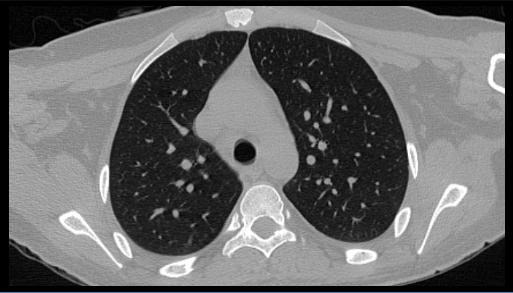

- Diagnostic imaging of the chest and abdomen revealed no additional abnormalities.